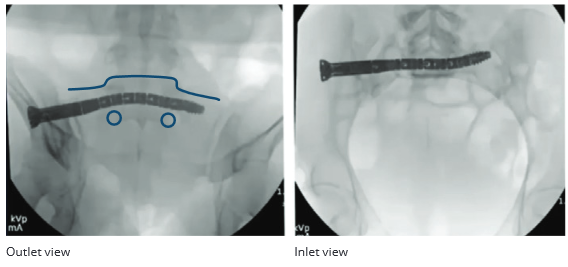

During insertion, the CurvaFix IM Implant curved to stay within the bone in the outlet view. It curved to stay within the cortical corridor posteriorly as can be seen in the inlet view in of this patient with dysmorphic anatomy.

CASE COMPLETION IMAGING

The CurvaFix IM implant (110 mm in length) curved to be in the correct position in the outlet view. In the inlet view, the CurvaFix IM Implant curved posteriorly to stay within the sacrum.